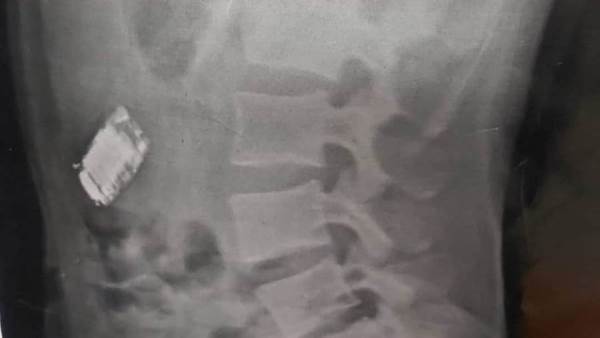

تمكن فريق من أطباء هيئة المستشفيات التعليمية، من استخراج هاتف محمول من جوف سجين في شبين الكوم بعد عملية جراحية استغرقت وقتًا طويلًا.

وخضع السجين، صاحب الـ20 عامًا، للعملية بعدما ابتلع الموبايل الصغير ملفوفًا في كيس بلاستيكي لإخفائه.